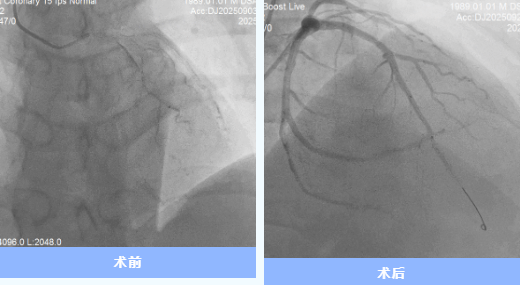

患者到院后,團(tuán)隊(duì)立即實(shí)施急診PCI手術(shù)。術(shù)中造影顯示前降支近端完全閉塞,雖經(jīng)球囊擴(kuò)張、血栓抽吸等操作,仍出現(xiàn)“無復(fù)流”現(xiàn)象。IVUS檢查提示冠脈內(nèi)彌漫性血栓,團(tuán)隊(duì)討論后決定暫不植入支架,先開展強(qiáng)化抗栓抗板治療,待后續(xù)復(fù)查造影。

9月24日,經(jīng)過充分的術(shù)前評估,心內(nèi)科一病區(qū)介入團(tuán)隊(duì)為代先生復(fù)查冠脈造影并于前降支成功植入支架1枚。